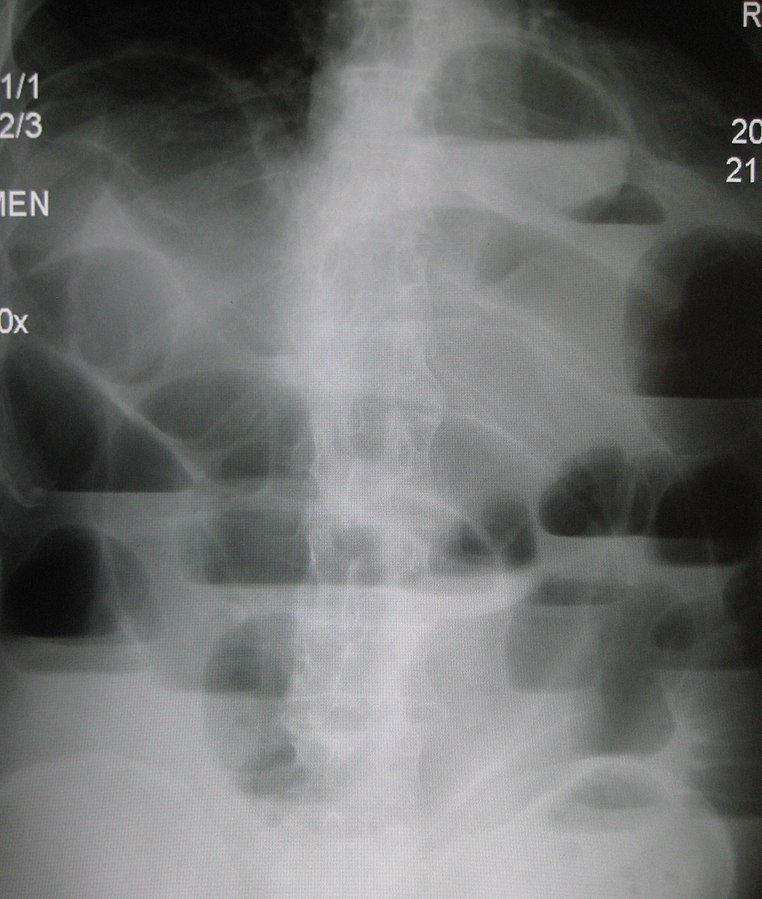

Image - An erect abdominal x-ray showing small bowel obstruction

Creative commons source by James Heilman, MD [CC BY-SA 4.0 (https://creativecommons.org/licenses/by-sa/4.0)]

A CT scan of the abdomen is the first line imaging choice when small bowel obstruction is suspected as it often allows the identification of the cause of obstruction. The exception to this rule would be if bowel perforation is suspected (e.g. if the pain is disproportionate and unremitting), in which case emergency surgical management may be performed without a CT scan, or an abdominal x-ray may be taken. Classically, an erect chest x-ray searching for pneumoperitoneum would have been undertaken to check for perforation, but this is performed less often today because it is not reliable.

Small bowel obstruction is considered a gastrointestinal emergency because of the high risk of complications such as dehydration/metabolic alkalosis, sepsis, bowel ischaemia/necrosis and perforation.

Management of small bowel obstruction is cause dependent but is often surgical.